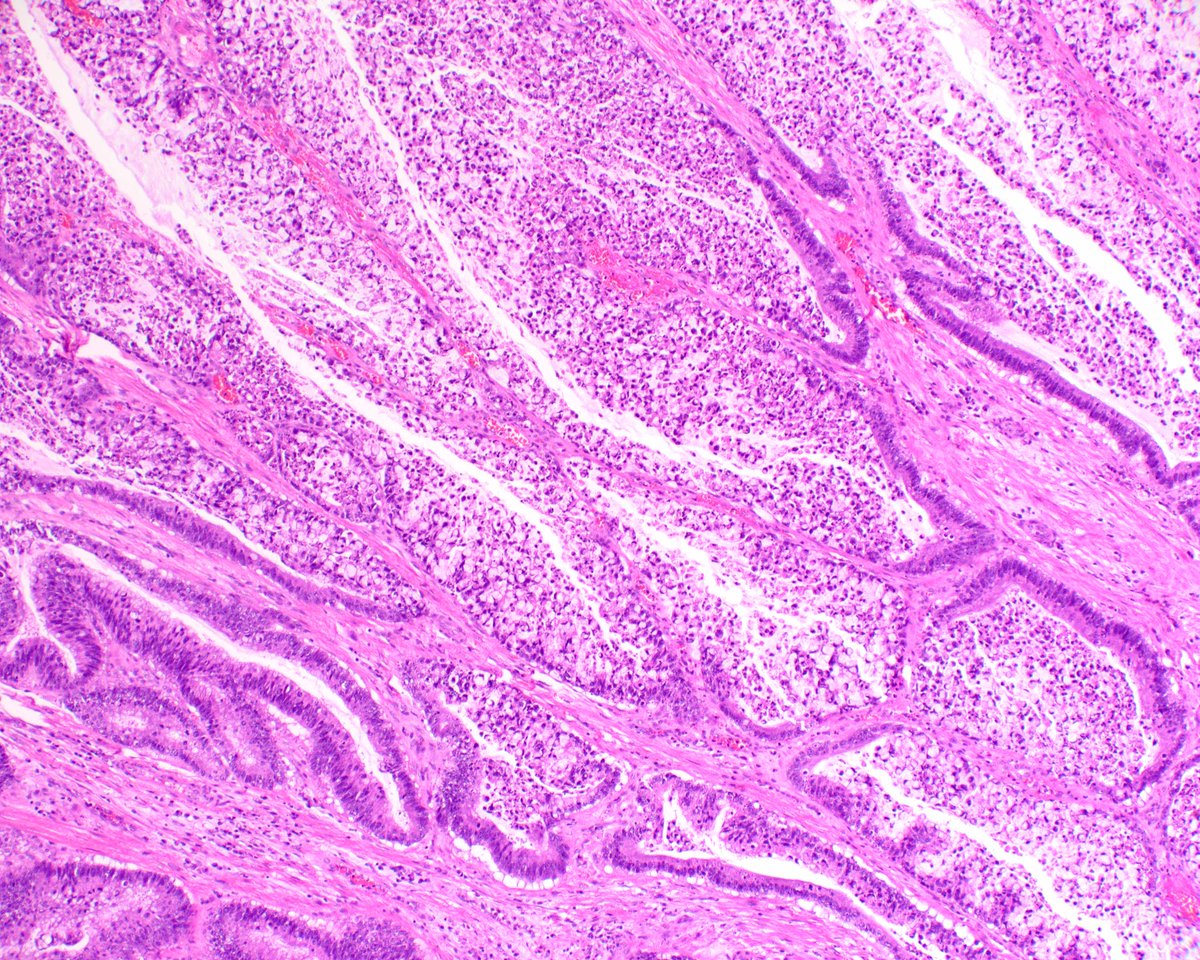

Placental Site Trophoblastic Tumor • RARE malignant trophoblastic neoplasm from intermediate trophoblasts • Mean Age: 31 • 2/3 cases follow full term pregnancy (median latency 12-18 months) • 🩺: Vaginal 🩸, uterine enlargement • ~25-30% may develop recurrent dz

2

23

68